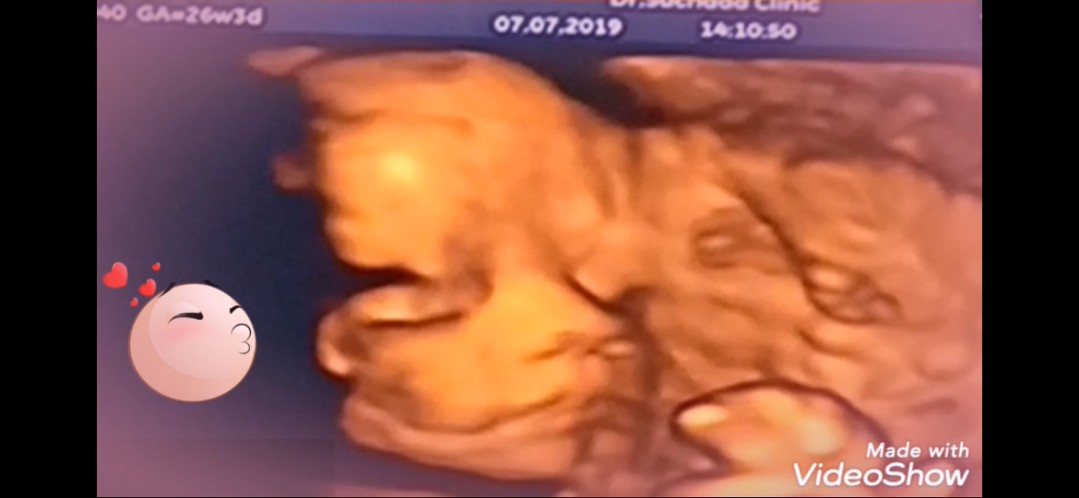

ซาวด์ตอน26wค่ะ

26 สัปดาห์ค่ะ